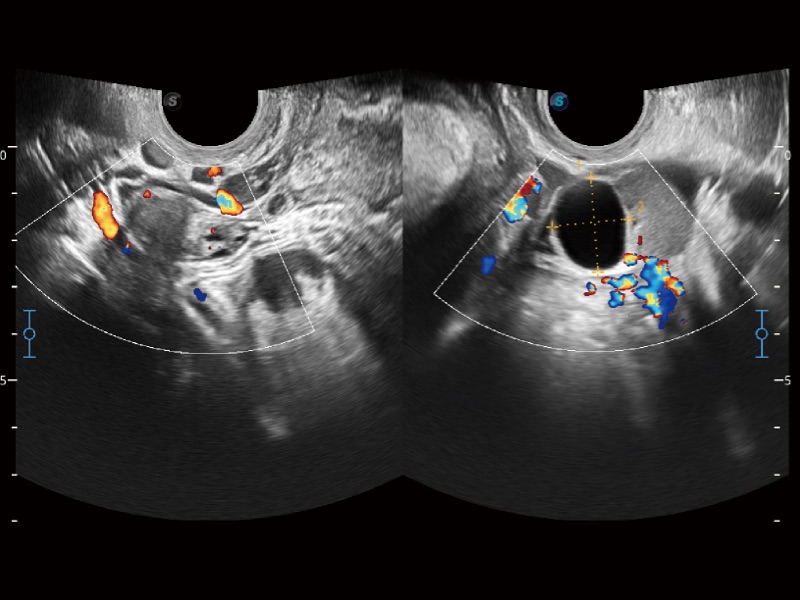

• SR Flow 高分辨率血流成像技术

高分辨率血流成像技术提高了对低速血流信号的检测能力。在提高空间分辨率的同时,也克服了血流外溢现象,为用户提供更加真实的血流动力学信息。

• 妇产科应用

临床图